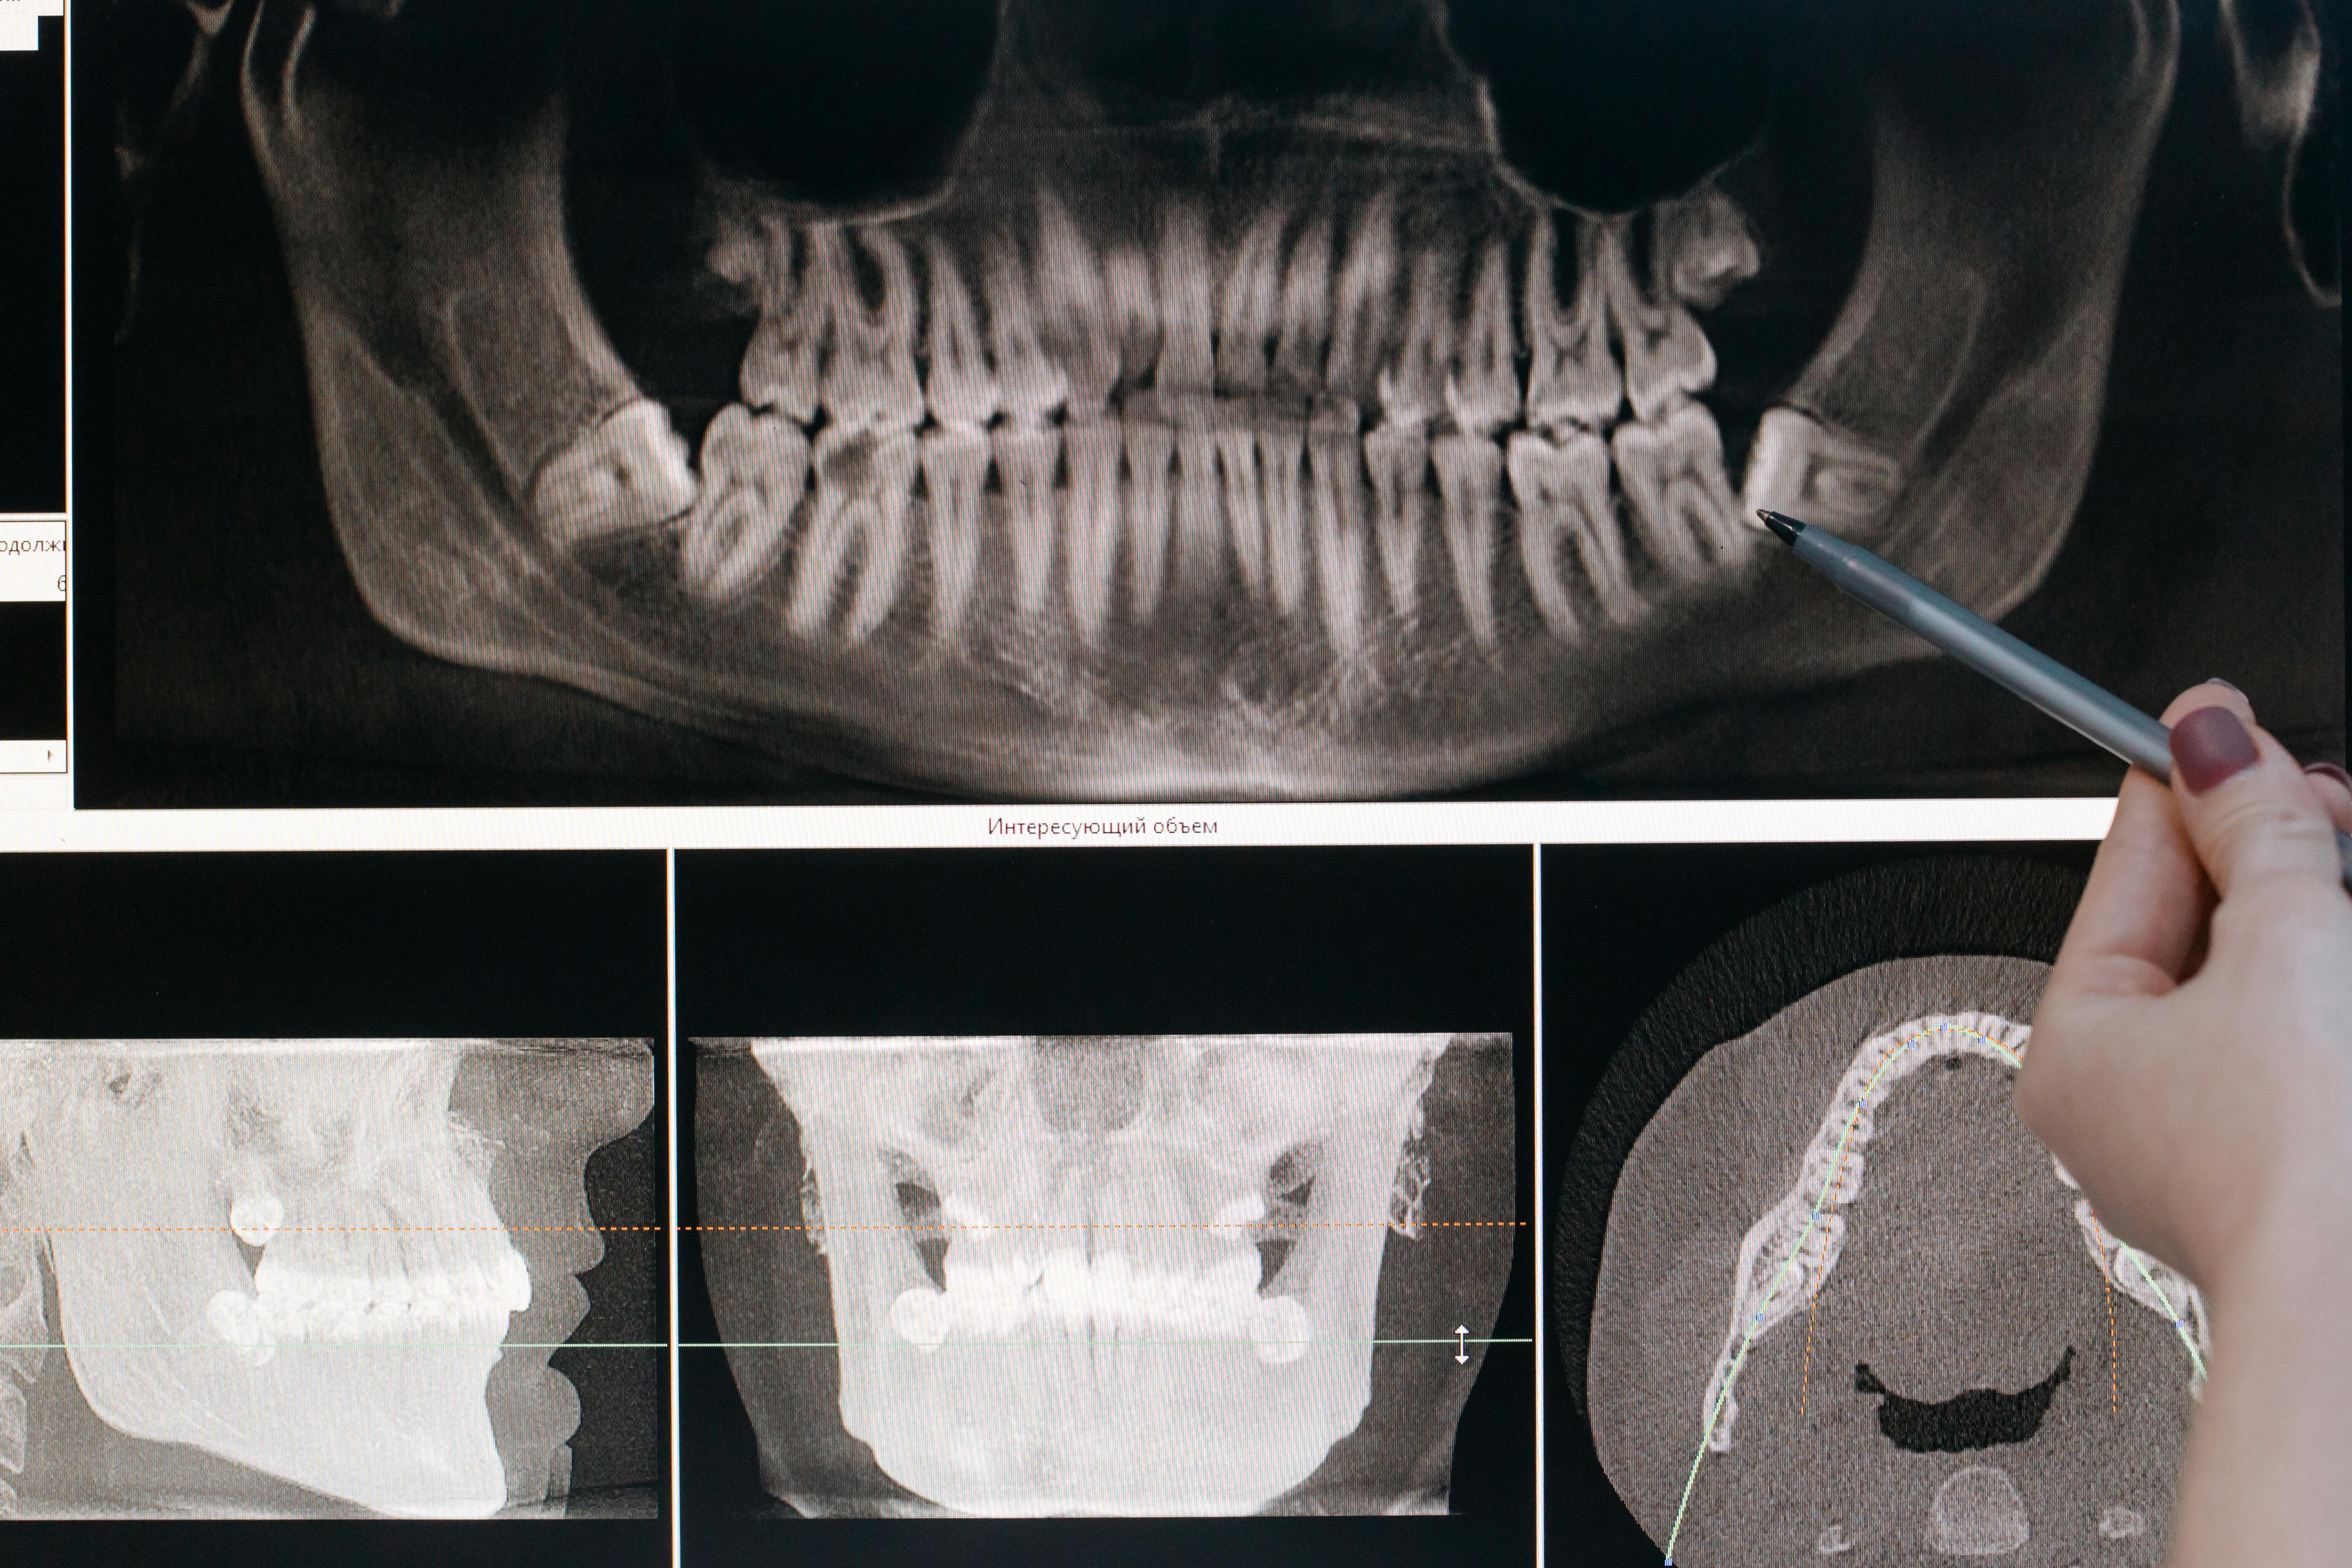

• Radiologia

La diagnosi accurata è il primo passo per cure dentali efficaci e sicure. La radiologia odontoiatrica permette di visualizzare ciò che non si vede a occhio nudo, garantendo trattamenti più precisi e personalizzati.